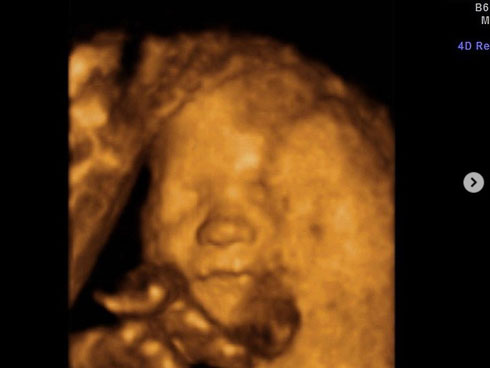

Fatma nói với các nhà điều tra rằng: "Tôi đang nấu cơm trong bếp. Trong lúc tôi không để ý, con gái tôi đã ngã vào trong chiếc xô đựng nước. Khi tôi tìm thấy thì con bé giống như một bào thai đang nằm trong xô, con bé lúc đó không hề có bất kì phản ứng nào. Ngay lập tức tôi bế con bé ra khỏi xô và cầu cứu sự giúp đỡ của hàng xóm. Tôi không thể tin nổi là con gái mình đã bị chết đuổi trong chiếc xô đó."